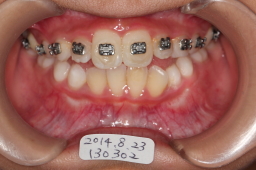

2014年08月23日

上顎切歯の空間が確保出来たので、ワイヤー除去